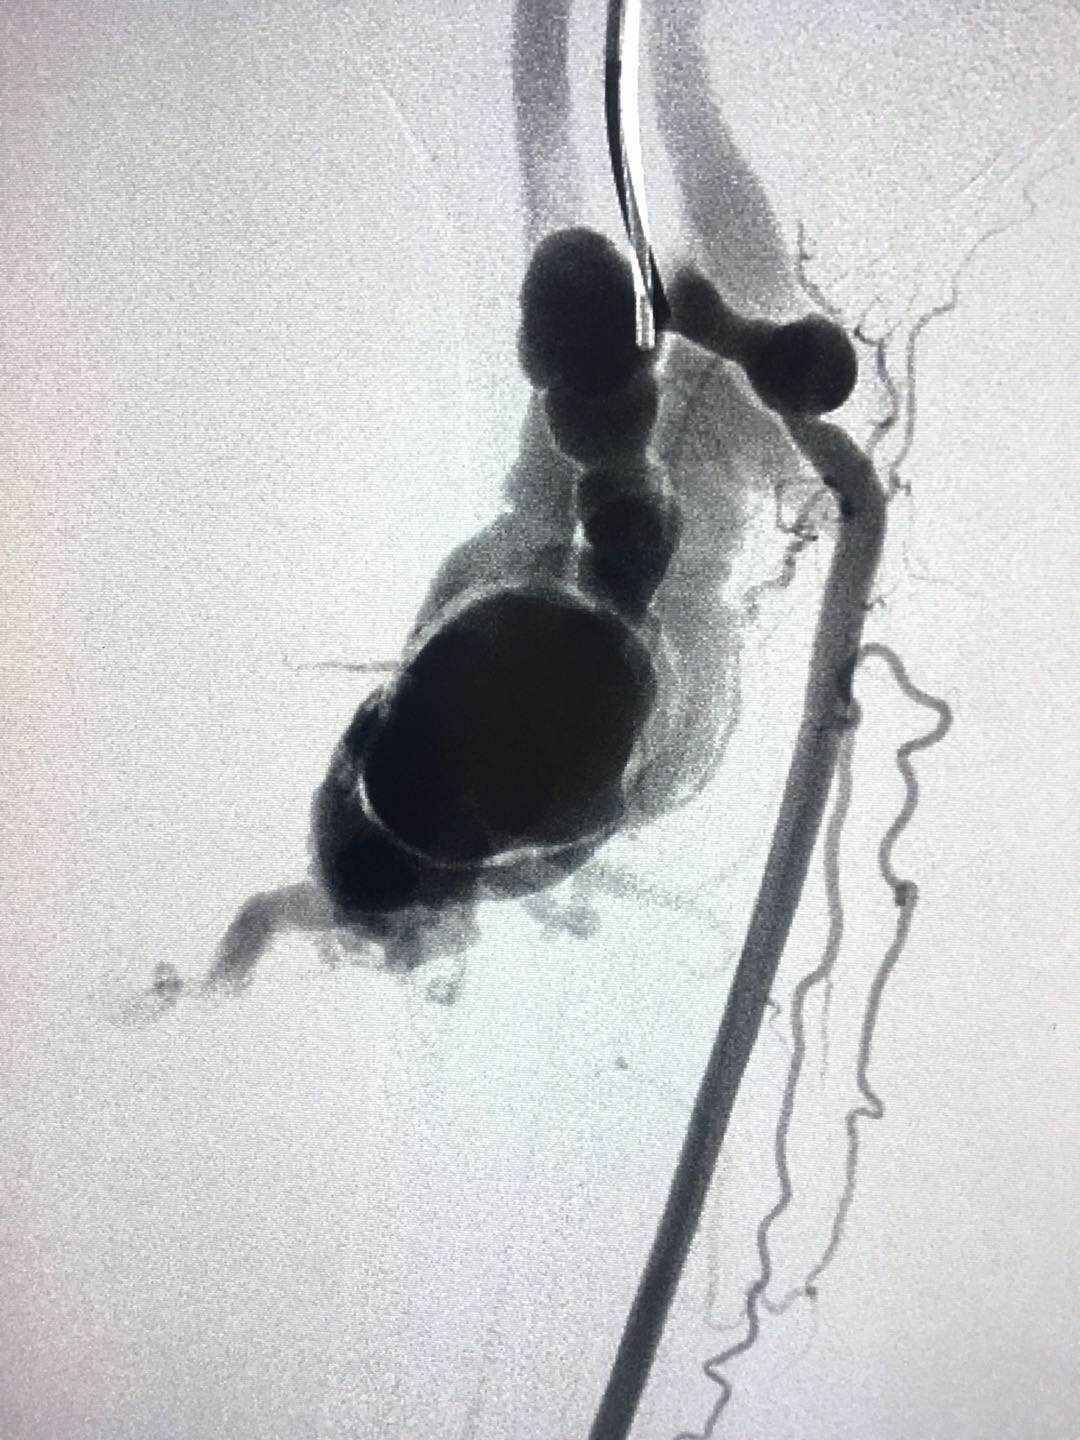

圖1:巨大血管瘤并動靜脈瘺